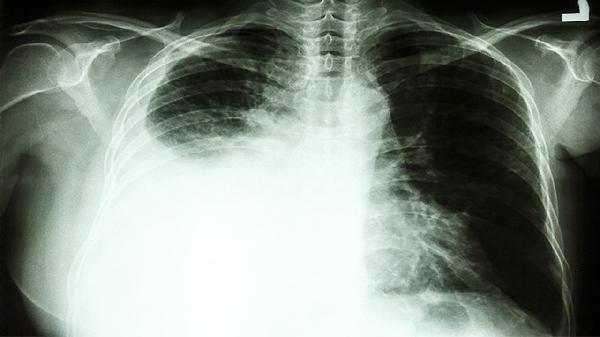

5、诊断与治疗:肾上腺肿瘤的诊断通常包括影像学检查如CT、MRI和激素水平检测。治疗方式根据肿瘤性质决定,良性肿瘤可观察随访,恶性肿瘤需手术切除,必要时结合放化疗。